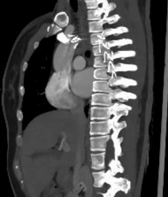

患者盆腔出血病情稳定一周后,经严格控制血压、稳定心率、卧床制动等治疗后,复查主动脉CTA提示主动脉夹层较前有所进展。主动脉疾病MDT团队——包括心血管外科、介入医学科、麻醉科、重症医学科(因患者合并骨盆骨折、血尿,还邀请了肾内科、泌尿外科、四肢关节骨科)等多学科专家进行了深入讨论,考虑该患者Stanford B型主动脉夹层累及范围广泛,如同体内“不定时炸弹”,具有限期手术干预指征,需要及时精确拆除。

△注:主动脉内膜呈螺旋形撕裂,夹层形成,随时可能因主动脉破裂、脏器缺血坏死等而危及生命。

经过周密计划,该科室制定了分阶段杂交手术方案:心血管外科先通过2处5cm的手术切口行颈动脉—锁骨下动脉搭桥,建立血流通路;接着介入科团队接力,通过3处不超过1cm的微创伤口完成胸主动脉夹层腔内覆膜支架隔绝术,并用血管塞精准封堵左锁骨下动脉起始段以避免术后支架内漏。

△注:支架精准定位,稳定释放,成功以“人工血管”将主动脉破口隔绝。

△注:患者出院后定期我科门诊复查,术后2月复查提示支架完美重建胸主动脉血管通路,原夹层内部基本血栓化,未发现相关并发症。